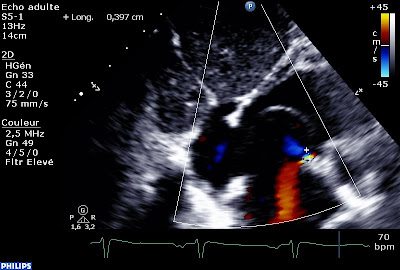

En coupe apicale des 4 cavités :